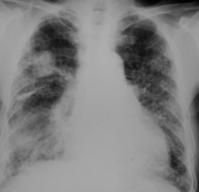

2.病理 病理检查报告很少。从棉尘暴露工人因其他疾病手术得到的肺大体标本可见,气管支气管壁上可有炎性细胞浸润,黏液腺增生,平滑肌萎缩。但这种改变很少扩展到肺段支气管,小叶中心性肺气肿很少见到。偏光显微镜下可见到棉花纤维。少数可见到棉尘小体(cotton-dust body),呈圆形或椭圆形,中心有铁染色阳性的黑蓝色核,外包黄色的蛋白外衣,一般认为没有诊断意义。个别报告见有肺泡壁纤维性增厚,晚期病例可见肺气肿、右心肥厚的表现。